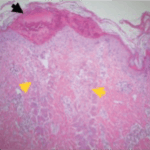

Immediately after treatment – Fractional laser energy creates micro-ablated columns to stimulate cellular regrowth. The surrounding healthy tissue promotes rapid healing.

Two days post-treatment – Skin is healing on the surface and creating new dermal collagen. This will continue for up to six months. The improved skin quality will make for a more youthful appearance.